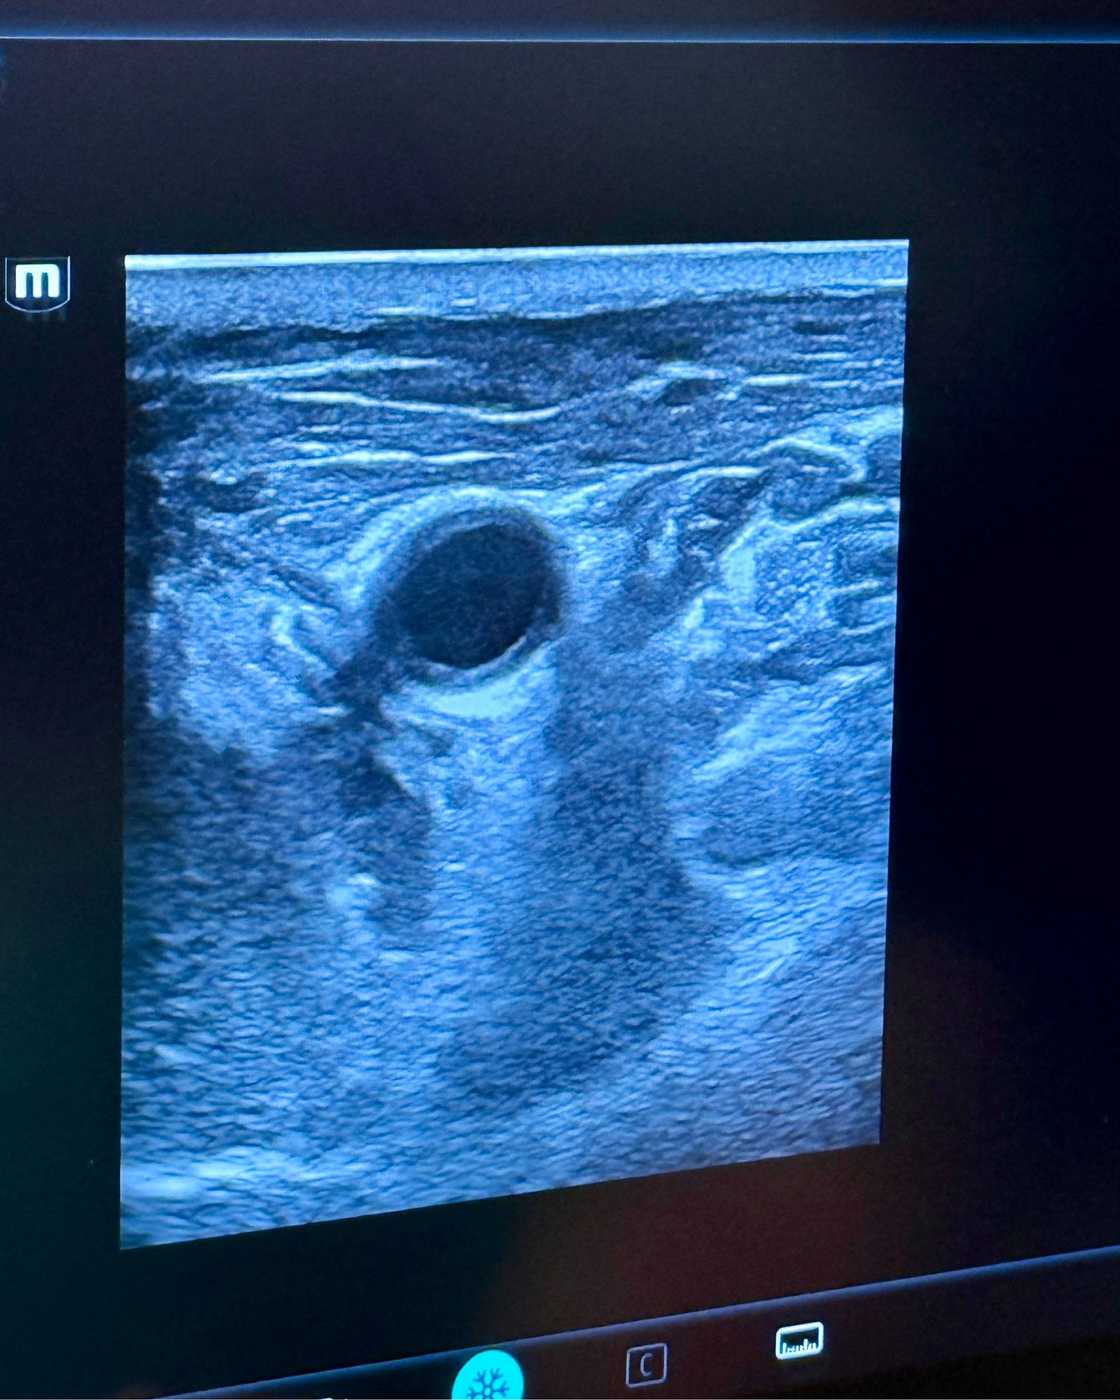

A specialised radiology team at the UCT Private Academic Hospital achieved this feat on 25 March 2026. They utilised advanced cryoablation technology to treat a patient suffering from a complex case of thyroid carcinoma.

This specific intervention represents the first time such a method was used for this cancer locally. The team performed the operation to eliminate secondary tumours that appeared after a previous surgical removal.

Dr Human and Dr Kassim led the specialised group during this medical milestone in Cape Town. They worked alongside Dr Bydawell and a dedicated interventional radiology team to ensure the clinical success.